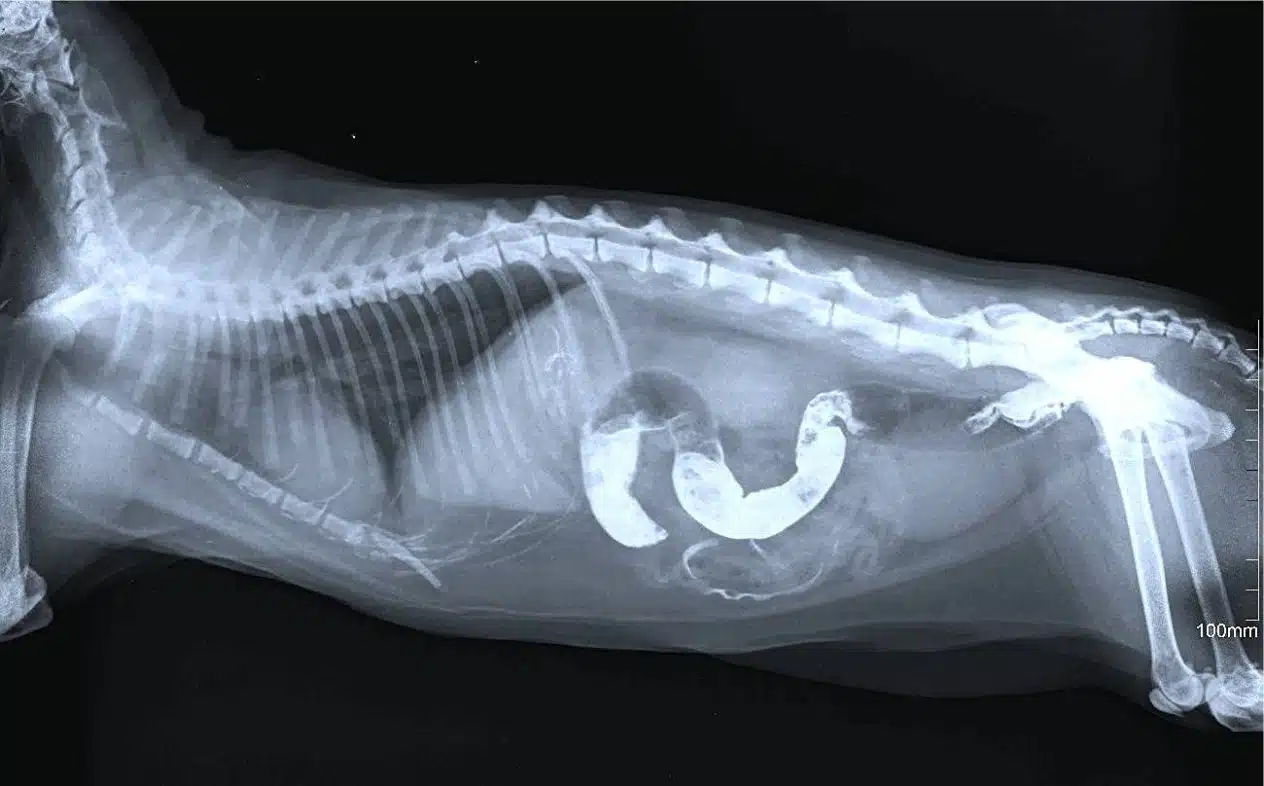

Gastric torsion – a critical condition that requires immediate attention

Stomach torsion (torsion) is an acute and very dangerous condition that occurs more often in large breed dogs with a deep chest. After active play or fast eating, the stomach expands from gas or food and then twists around its axis. As a result, the blood supply is cut off and the organ begins to die.

– the stomach swells sharply, becomes very hard;

– the dog salivates, tries to vomit, but is unsuccessful;

– restless behavior changes to depression.

This is an emergency situation. You cannot wait – you need to go to the vet immediately. Every minute counts.